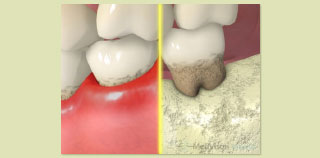

歯周病の進行段階

プローブという器具を使用して歯肉の中の状態を調べます。